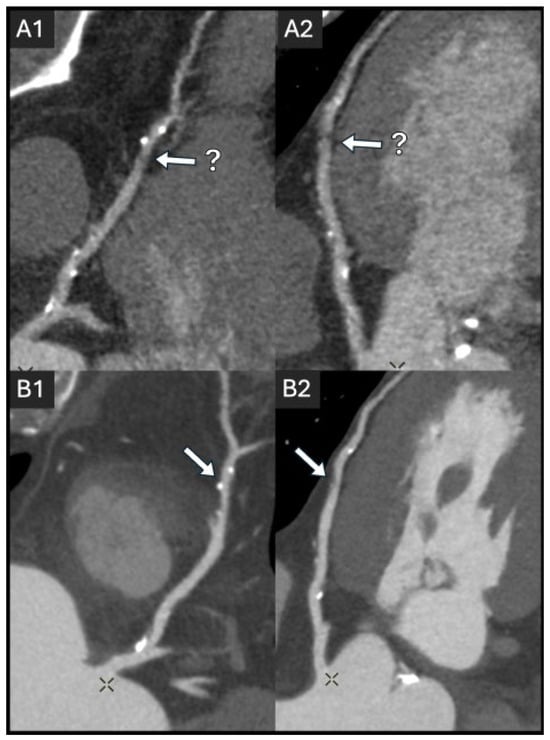

2.2. Coronary Lumen Attenuation